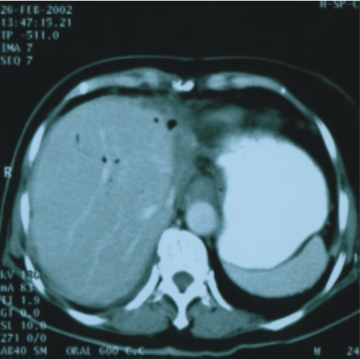

63歲/女性(肝內膽道癌) |

||

90/2/15(治療前) |

91/3/21(治療後) |

腫瘤大小:6x5x5公分 |

完全消失 |